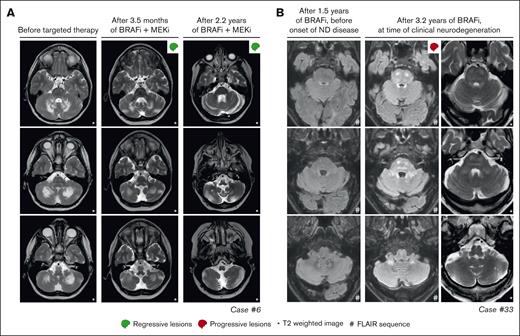

Response and progression of ND lesions. (A) Axial MRI images of case 6, with isolated ND-LCH showing significant reduction in T2-hyperintense lesions after treatment with dabrafenib and trametinib. Note that the remaining hyperintense lesion in the right cerebellum at last follow-up (right column; middle image) is related to the biopsy that was taken from this anatomical site. (B) Axial MRI images of case 33 showing the development of T2- and FLAIR-hyperintense lesions in the pons and cerebellum while receiving treatment with vemurafenib. The patient also developed clinical symptoms of neurodegeneration and died 7.5 months after the MRI scan depicting ND lesions was made. ND, neurodegenerative; FLAIR, fluid-attenuated inversion recovery.

In 4 of 27 patients with multisystemic and/or solid lesions, brain lesions characteristic of histiocytosis-associated neurodegeneration were present on MRI at targeted therapy initiation. Only 1 of 4 also had clear neurologic symptoms (patient 32 with dysarthria). During targeted therapy, radiologic response of the brain lesions was noted in case 17 (supplemental Figure 1A), whereas lesions remained stable in 2 of 4 and were not evaluated in case 32, who appeared to have a slight improvement in dysarthria. One of the patients with stable brain lesions during targeted therapy (patient 14 with ECD) had progressive radiologic abnormalities in the pons and cerebellum at 4 and 7 months after stopping vemurafenib because of toxicity (supplemental Figure 1B). This patient did not have progressive neurologic symptoms; therefore, no treatment was initiated. At 2 years after stopping vemurafenib, the patient’s clinical and radiologic situation remained stable. Another patient (case 33 with LCH/ECD) developed new radiologic abnormalities in the pons and cerebellum and clinical symptoms of neurodegeneration after almost 3 years of treatment with vemurafenib (Figure 5B). The patient subsequently received (methyl)prednisolone and increased doses of vemurafenib (up to twice daily 720 mg; 4 out of 6 days), without a clinical response. Eventually, targeted treatment was switched to dabrafenib, but the patient requested euthanasia a few weeks later and died shortly thereafter.

Among the 8 patients receiving targeted therapy for ND-LCH, 2 had a PR of radiologic abnormalities (Figure 5A), 4 had stable lesions, and 2 stopped therapy before response could be evaluated (Figure 2). The 2 patients with a response were treated within 2 years after diagnosis of LCH, whereas the 4 with stable lesions started targeted therapy between 5 and 20 years after diagnosis of LCH. The radiologic response was accompanied by improvement of cognitive symptoms of memory impairment and concentration difficulties in case 10 (who did not have ataxia/dysarthria), whereas repeated neurologic assessments in case 6 showed a rather stable situation, with only slightly improved International Cooperative Ataxia Rating Scale scores (45 to 42).62